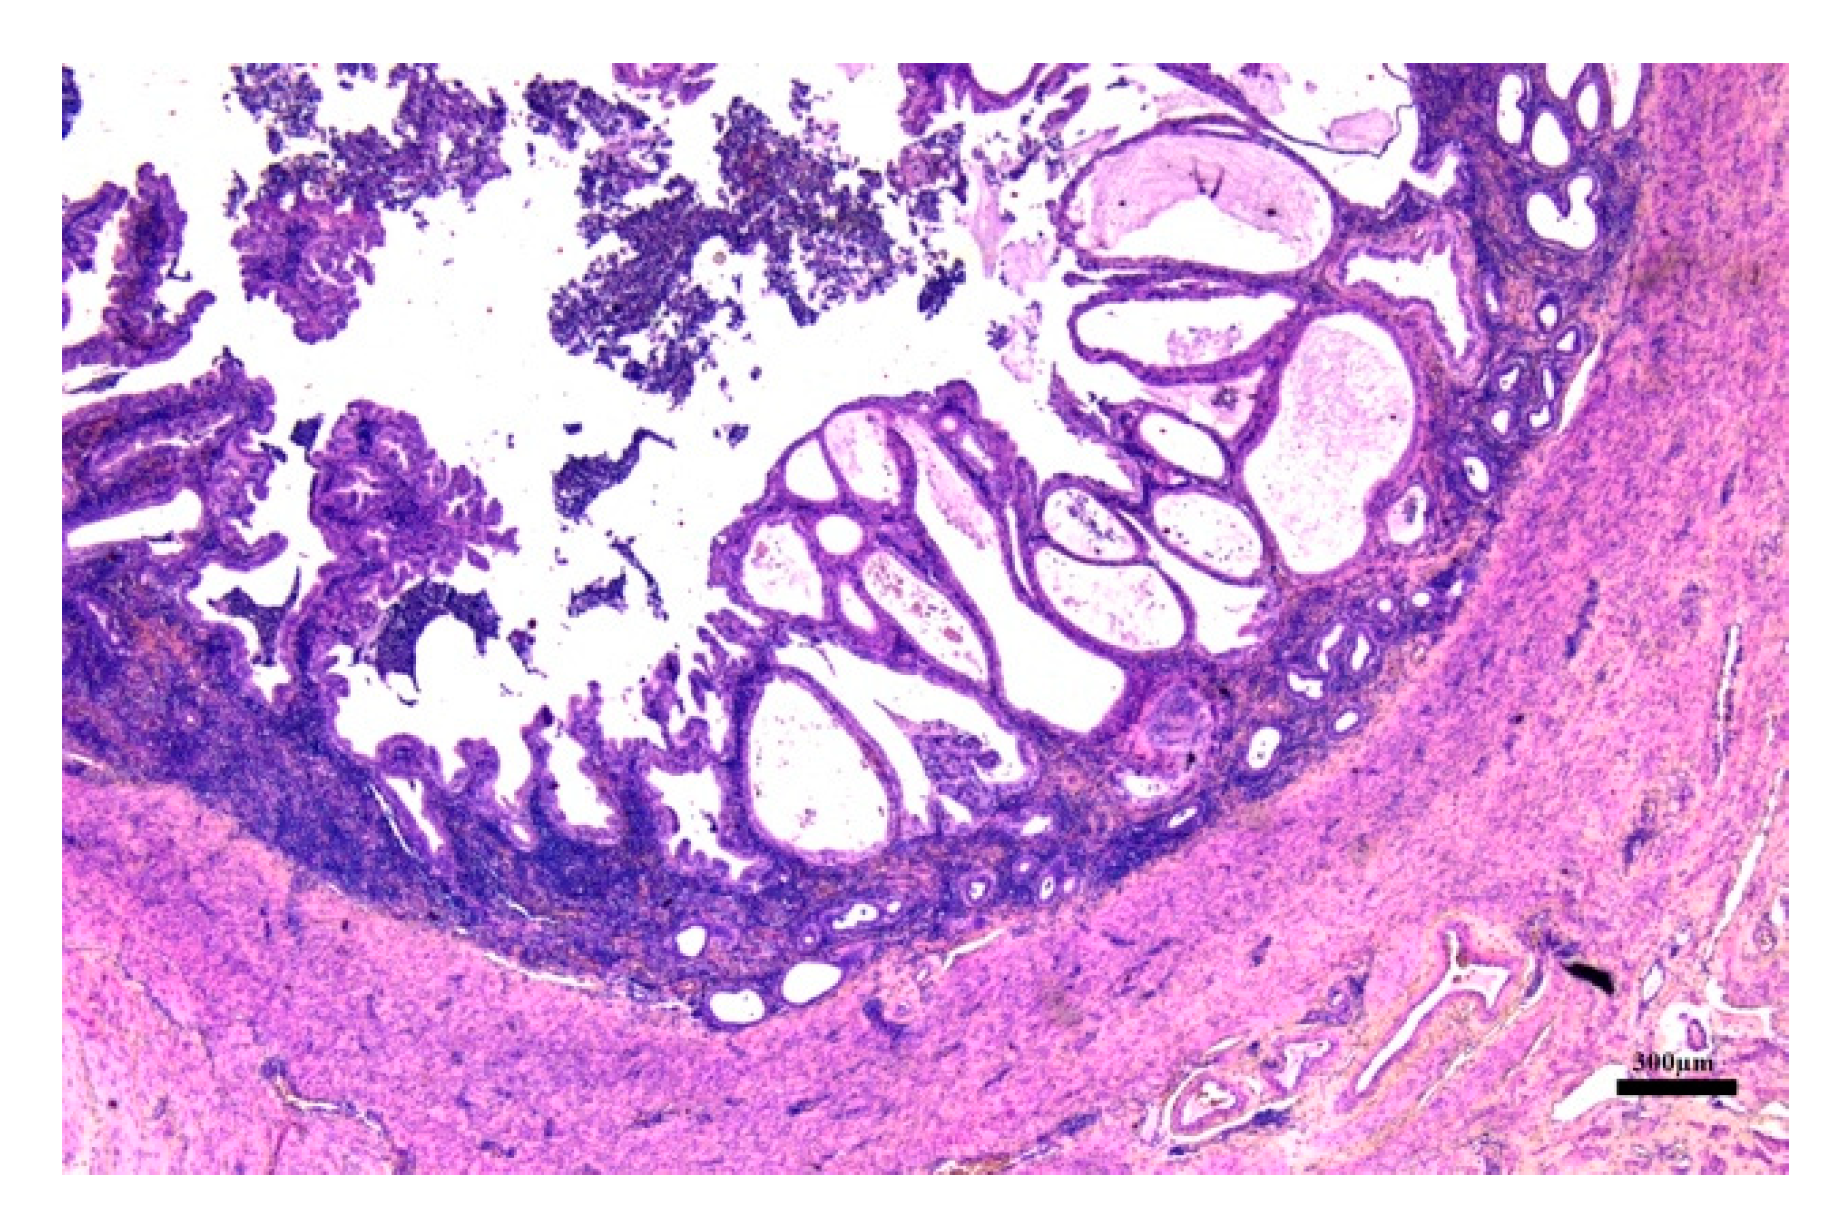

3.3. Histological Evaluation